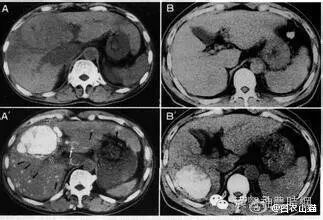

3.磁共振显像(MRI)  MRI在肝癌诊断中的作用日益受到重视,其诊断价值有超过CT的趋势。与CT相比其优点为:无电离辐射,能获得横断面、冠状面、矢状面3种图像,对肿瘤与肝内血管的关系显示更佳;对软组织的分辨力高;对肝癌与肝血管瘤、囊肿及局灶性结节性增生等良性病变的鉴别价值优于CT。国外报道MRI对大于2cm的肝癌的检出率为97.5%,小于2cm者为33.3%,检出最小的肝癌为1.5cm。近年有采用钆离子螯合剂作对比增强剂成像,提高了MRI对微小病灶的检出率,并有助于肿瘤性质的判断。原发性肝癌在T1加权像上多为低信号占位,少数可为等信号或高信号,坏死液化信号更低;伴有出血或脂肪变性则局部呈高信号区;钙化表现为低信号。在T2加权像上,绝大多数肝癌表现为强度不均的高信号区,少数可呈等信号区;液化坏死区信号强度很高;钙化则为点状低信号。门静脉或肝静脉癌栓在T1加权和质子密度像上呈稍高的信号;在T2加权像上为较低的信号强度。假包膜在T1加权像表现为肿瘤周围的低信号带,在T2加权像上内层纤维组织为低信号带,外层丰富的受压的小血管或胆管则为高信号带。MRI T1加权像可显示清晰的肝脏血管解剖,对指导手术有很大的参考价值。